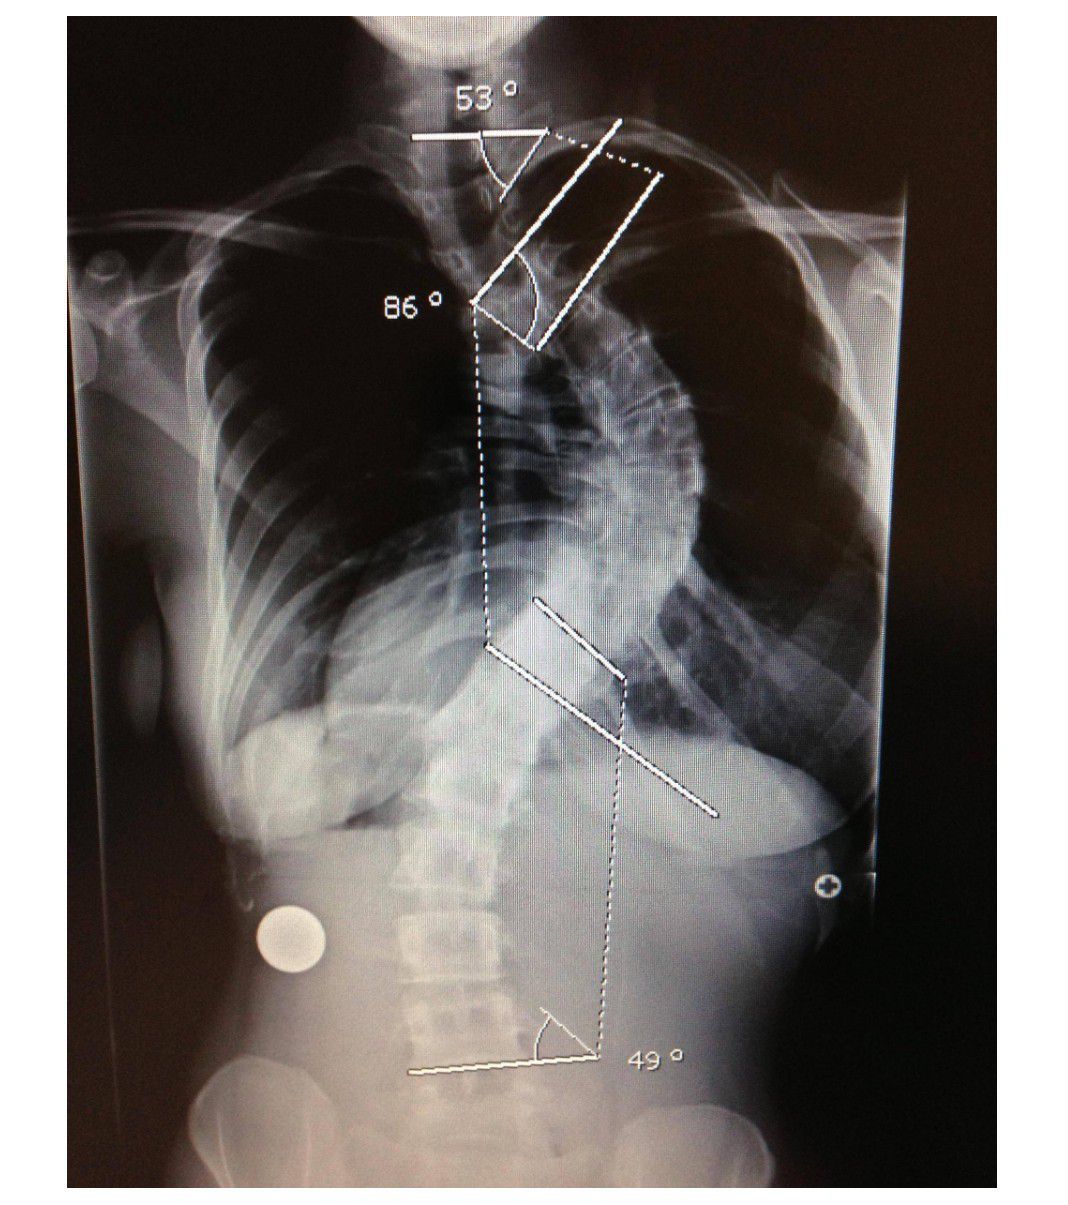

Scoliosis, a sideways curve of the spine that may take the form of a letter “C” or “S”, is a common condition affecting many pre-teens and teens. In some cases, patients will have surgery to lessen the curve and prevent it from worsening. One patient bravely revealed photos of both her pre-op and post-op body in postings to Imgur. Teens considering the surgery for themselves might want to see the simple story of how someone else successfully moved through both her surgery and her recovery period... not an easy thing to do for anyone! #1